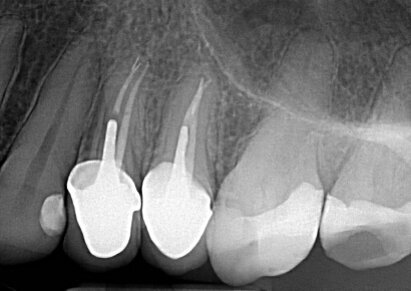

Dopo un ritrattamento canalare (Fig. 2) dei due premolari e un dente ricostruito con perno-moncone fuso (Fig. 3), sono stati posizionati due provvisori.

Fig. 2: Radiografia dei ritrattamenti canalari.